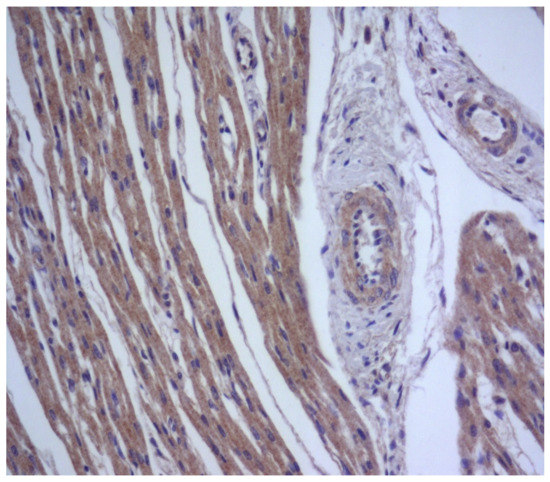

The Epstein–Barr virus (EBV) may result in infectious mononucleosis coupled to markedly affected lymphoid tissue and parenchymal organs [49]. It may persist throughout human life and cause severe chronic active infection of myocardial CD8+ T cells during ongoing perimyocarditis [50]. During myocarditis, expression of EBV antigens is detected in cardiomyocytes, lymphocytes, and vascular endothelium (Figure 4).

Figure 4. Expression of Epstein–Barr virus antigens (brown staining) in cardiomyocytes, lymphocytes, and endotheliocytes in generalized Epstein–Barr virus infection. IHH, mouse monoclonal anti-EBV (Thermo, Waltham, MA, USA), DAB. SW. ×200.